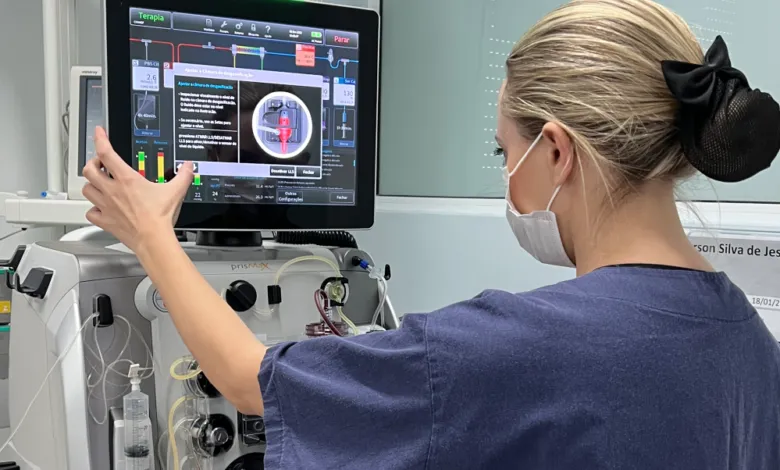

Hemodiafiltração exige ajuste de dose dos medicamentos? O que um caso de vancomicina pode nos ensinar

Hemodiafiltração exige ajuste de dose dos medicamentos? O que um caso de vancomicina pode nos ensinar

A hemodiafiltração pode aumentar significativamente a depuração de diversos medicamentos, levando a subdosagem quando usamos protocolos baseados em hemodiálise convencional. Entender a farmacocinética da droga e a prescrição da HDF é essencial para evitar falha terapêutica e ajustar corretamente as doses.